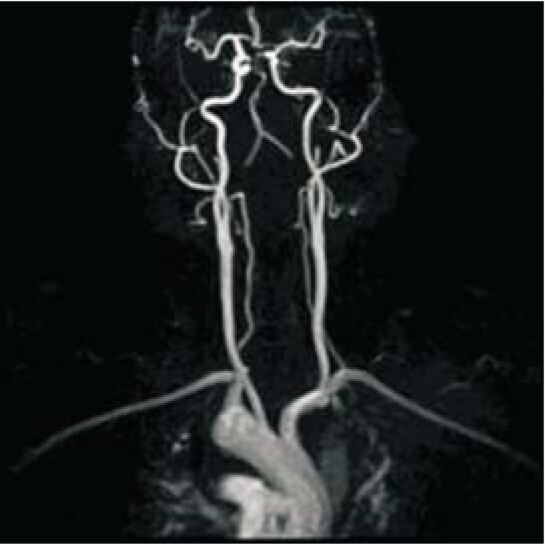

SuperMark 1.5T is a latest generation superconducting MRl system based on over 30 years of experience in research and development, which focuses on user's concerns. This system is equipped with a new upgraded hardware and software platforms with A-combi and Al technologies that benefit users a lot and deliver patients with more comfortable experiences. It features new user-friendly design, faster imaging speed, higher image quality and greatly improved work efficiency.

SuperMark 1.5T provides not only conventional pulse sequences and basic clinical applications, but also advanced functional applications. Moreover, it adopts brand new professional APEX operation system which ensures easy operation and fast diagnosis